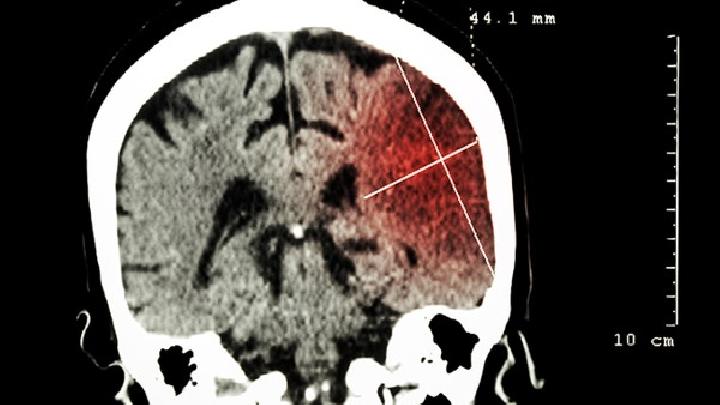

颅内静脉窦血栓

发病部位在哪里?

头部

应该挂什么科?

神经内科、神经外科

应该做哪些检查项目呢?

头部CT